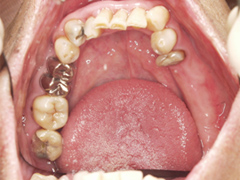

写真(1)口内写真

吉本歯科医院では、口内写真とパノラマレントゲンを撮影し、まずは顎の骨の状態まで詳しく確認しました。